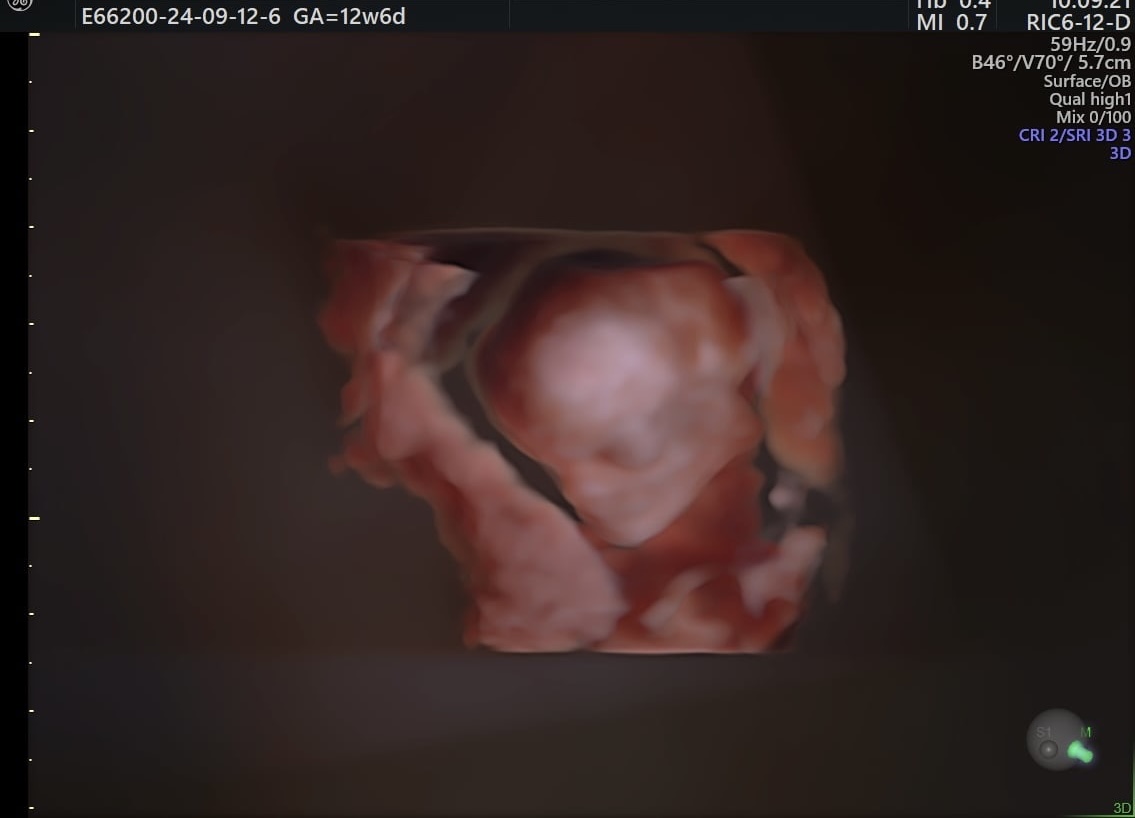

Ahojte, aj ja som ešte tu 🙂 V stredu budem 11 tt a idem na 3d ultrazvuk tak vám sem potom pridám nové foto. Ja som stále ospalá, hladná a taktiež je mi stále na grcku ale inak sa babo drží pekne z čoho sa nesmierne tešíme🙂

@klarka0002 suppeer, ja reku už zmizol každý 😂 ja už pomaly 14tt .. to budeš mať zážitok 🙂 bolo to krásne .. nám akurát vyšlo, že mal otec vyšetrenie v KE mama kadernicku a mme vyšlo sono, tak sme boli spolu .. dokonca sestrička zavolala dnu aj ich 😂 boli sme jak v kine 🙈

@nikadominikanika To je pekné 🙂 hej, videla som tvoju fotku, je krásne vidieť cele babo. Už aj vieš čo to bude? My sme boli na genetike tak nám hneď povedali ze to bude chlapec. Mame ešte 1 embryo zmrazené a to ma byt tiez chlapček.

@nikadominikanika Krásna tvárička, och...určite sa nevieš vynadívať.

@klarka0002 no zatial mi príde ako mimozemštaník 😄😄 ale rak v tomto štádiu je to nornalne 😄

@klarka0002 tak to je super foto ❤️